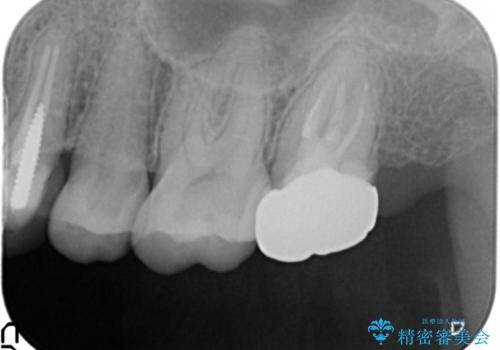

精査したところ、奥歯のメタルインレー(銀の詰め物)の下でう蝕が広がっていました。

自然な仕上がりと咬み心地にご満足頂けました。

セラミックインレーは審美的で強度が高いだけではなく、適合が良いため二次う蝕にもなりにくいです。

インレーの種類:セラミックインレー e-max press